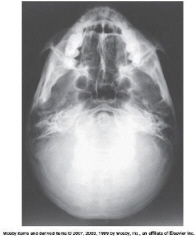

the six areas of incomplete ossification in a newborn infants skull are called

frontanels